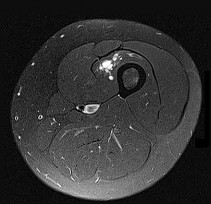

This patient has a dedifferentiated liposarcoma within a preexisting atypical lipomatous tumor. The imaging demonstrates a large fatty mass with increased internal septations proximally (the atypical lipomatous tumor) and a solid enhancing mass distally (the dedifferentiated portion). A biopsy reveals a high-grade liposarcoma. The other diagnostic responses do not reflect sarcomatous transformation of the lesion.

Surgical treatment of a high-grade sarcoma involves wide surgical resection. Radiation decreases local recurrence but does not clearly influence overall survival. The role of chemotherapy in high-grade soft-tissue sarcomas remains investigational; there is a modest (8%-15%) associated improvement in overall survival.

Intramuscular lipomas and atypical lipomatous tumors are treated with marginal resection alone. Radiation therapy for soft-tissue sarcomas may be given before or after surgery. When administered before surgery, patients have a higher wound complication rate but better long-term function attributable to lower rates of lymphedema, fibrosis, and contractures.